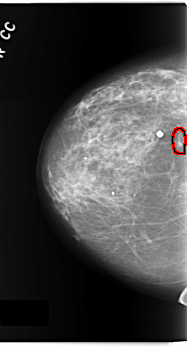

FILE: C_0171_1.RIGHT_MLO.OVERLAY

TOTAL_ABNORMALITIES 1

ABNORMALITY 1

LESION_TYPE CALCIFICATION TYPE PLEOMORPHIC DISTRIBUTION CLUSTERED

ASSESSMENT 4

SUBTLETY 4

PATHOLOGY MALIGNANT

TOTAL_OUTLINES 1

BOUNDARY